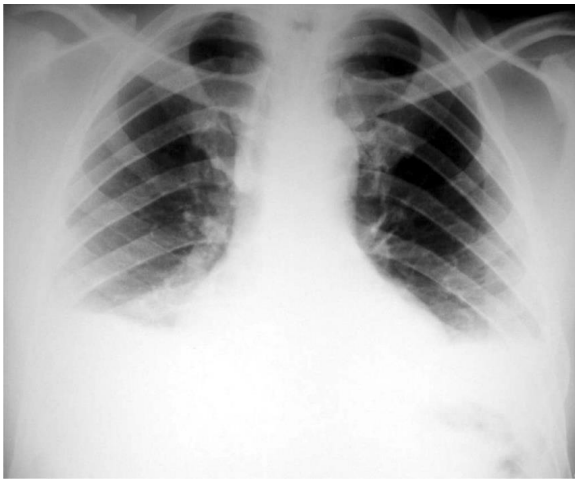

Leia o caso que segue para responder às questões 21 e 22.

Paciente do sexo masculino, 67 anos de idade, refere, há cerca de 3 meses, dispneia progressiva até moderados esforços, associada com tosse seca, ortopneia, dispneia paroxística noturna e edema de membros inferiores bilaterais. Nega febre, escarro e chiado no peito. Refere ter HAS (hipertensão arterial sistêmica), mas faz uso irregular de anti-hipertensivos. Ex-tabagista 20 maços/ano, abandonou o vício há 15 anos. Nega patologias pulmonares prévias. Ao exame está em regular estado geral, eupneico, saturação periférica de oxigênio 92% em ar ambiente, FC: 90bpm, FR: 20 irm, PA: 180x100mmHg; ausculta pulmonar: estertores finos bibasais; ausculta cardíaca: ritmo cardíaco regular, 2 tempos; membros edema bilateral simétrico de membros inferiores 3+/6+.

Vem na consulta com os seguintes resultados de exames:

Espirometria:

Pré-broncodilatador: CVF 3,30 (85%)-VEF1 3,20 (80%) – VEF1/CVF 88%

Pós-broncodilatador: CVF 3,40 (86%)- VEF1 3,22 (82%) -VEF1/CVF 85%

Raio-X de tórax

Qual deve ser a conduta inicial para esse paciente?

O diagnóstico mais provável para esse caso é de